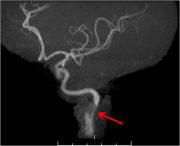

So why am I calling pulmonary emboli a false vascular emergency? Well, I am eluding to the way some patients with pulmonary emboli are being treated. Sometimes patients with pulmonary embolism are treated much more aggressively than their situation mandates. Most patients with pulmonary embolism will do just fine when treated with anticoagulation. Some less common patients obviously need thrombolysis. These are true vascular emergencies and are hard to miss. But there is a group in the middle of patients with submassive pulmonary emboli. The treatment of these patients represents a debate. But because of submassive pulmonary emboli, some patients with low-risk pulmonary emboli are still being treated very aggressively as if they were a vascular emergency. Sometimes these patients suffer unneeded complications. Sometimes imaging drives treatment instead the patient’s clinical presentation. For instance, the saddle PE in the picture above may or may not represent a patient with massive PE. It may or may not represent a true vascular emergency. Complications caused by over zealous clinicians, on the other hand may represent such emergencies…